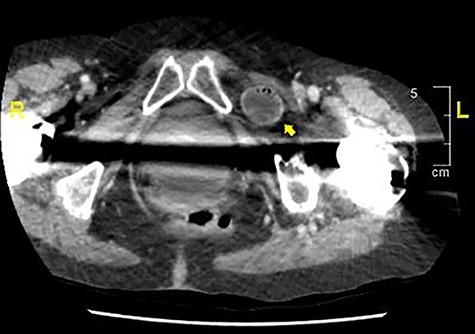

On initial presentation, her blood results were as follows: white cell count (WCC) 14.8 × 109 cells/l (RR 4.3–11.2 cells/l), neutrophils 12.3 × 109 cells/l (RR 2.1–7.4 cells/l) and C-reactive protein (CRP) 1.9 mg/l (RR 0–5 mg/l). Imaging performed included an abdominal film, which showed nonspecific bowel gas pattern (Fig. 1). The patient was managed conservatively and discharged home. She represented 2 days later with worsening symptoms and blood results of WCC 20.1, neutrophils 18.4 and CRP 6. She was admitted under the surgical team and a thoracic and abdominal CT scan was done (Figs 2–4). It was initially reported as significant dilated small bowel loops in keeping with small bowel obstruction due to a femoral hernia. However, the scan was revisited by the surgical team in more detail as the images appeared to represent an obturator hernia. Upon further discussion, these findings were corroborated by the radiologist and a strangulated left obturator hernia was identified.

Distended stomach and dilated bowel loops with an obturator hernia (pointed by the arrow), as shown in the sagittal section.